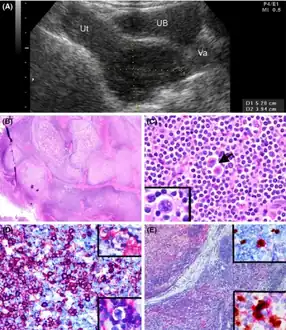

a-e)Clinicopathologic features of cervical nodular lymphocyte-predominant Hodgkin lymphoma

a-e)Clinicopathologic features of cervical nodular lymphocyte-predominant Hodgkin lymphoma Hodgkin lymphoma, nodular lymphocyte predominant (low power view). Notice the nodular architecture and the areas of "mottling". (H&E)